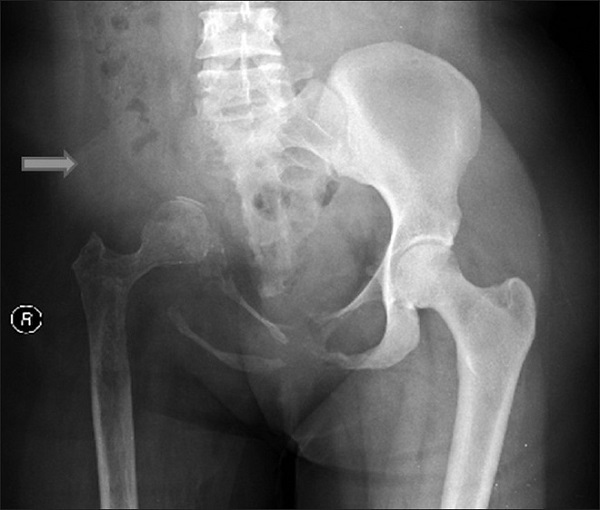

Bệnh nhân này là một người phụ nữ 44 tuổi hoàn toàn khỏe mạnh. Cô đi khám vì cảm thấy đau tăng dần ở vai trái. Kết quả chụp XQ khớp vai cho thấy tổn thương tại xương đòn, và bác sĩ lập tức nghĩ đến chẩn đoán ung thư. Tuy nhiên, kết quả sinh thiết lại cho kết luận không rõ ràng. Lần sinh thiết lại vào vài tháng sau đã có kết quả âm tính. Nhưng mọi chuyện chưa dừng lại ở đó, khi cơn đau của bệnh nhân tiếp tục dai dẳng.

Và đây là lúc điều kỳ quái diễn ra: 18 tháng sau, bệnh nhân tới tái khám và phát hiện ra xương đòn và đầu trên xương cánh tay đã biến mất hoàn toàn trên phim chụp XQ. Cơn đau thì vẫn âm ỉ, và thậm chí bệnh nhân còn nhận thấy tay mình phù nề và tấy lên, dù chỉ bị va đập nhẹ.

Chỉ khi sử dụng đến những kỹ thuật chẩn đoán hình ảnh cao cấp, các bác sĩ mới tìm ra vấn đề: các mạch máu tân tạo đã phát triển quá mức, và che mờ hình ảnh của các xương này trên phim chụp. Và kết quả sinh thiết cho thấy, căn bệnh kỳ lạ này có tên là bệnh Gorham-Stout.